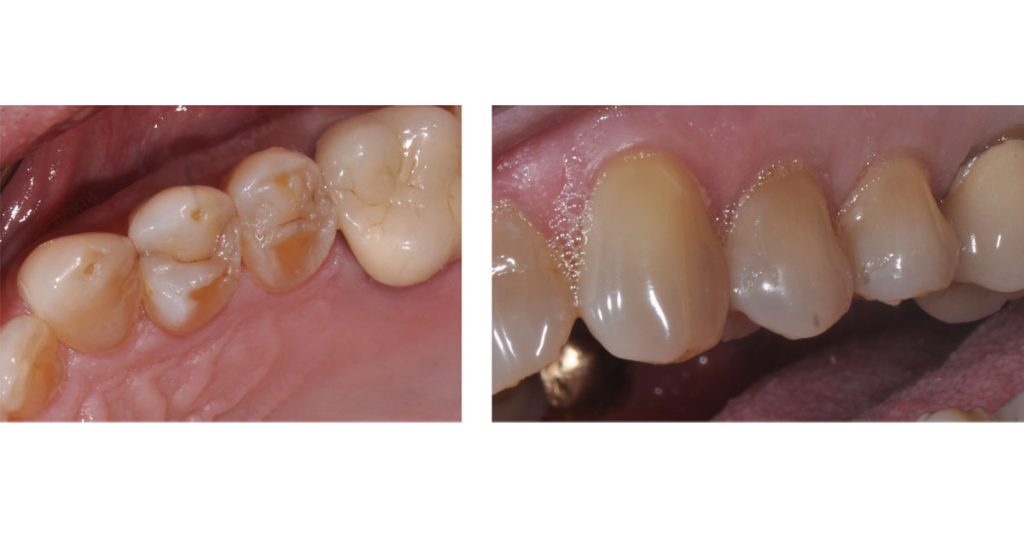

The photos above show the pre-treatment tooth and the required cuspal coverage due to enamel erosion. The diagnostic wax-up provides a preview of the desired outcome. Note the cuspal height changes that are to be incorporated into the final restoration. This is a key observation! Ceramic restoration failures occur due to inadequate reduction related to final-outcome contours.

Long-term predictability may be achieved by incorporating proper planning and design into the posterior partial coverage ceramic restorations. This patient had significant erosion due to gastroesophageal reflux disease.

He had lost cuspal height and contour. The full-contour e.max ceramic onlays were fabricated with adequate thickness and ideal anatomy using the diagnostic wax-up as a guide for outcome-based tooth preparation. These restorations have now been functional for more than five years.

The following photos show the final ceramic onlays for the patient’s #12 and #13 teeth: